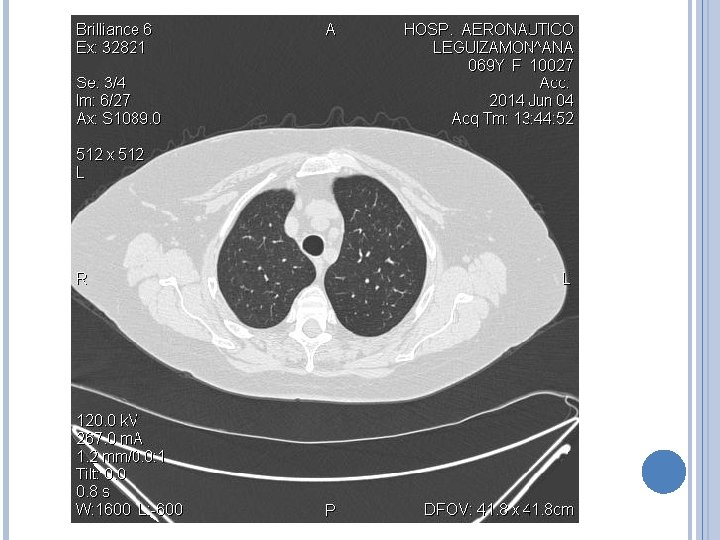

IMAGENES